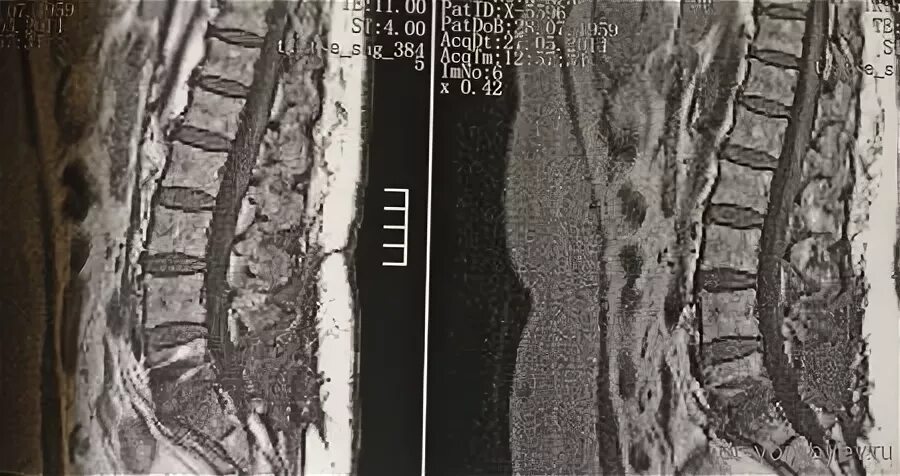

Изменения по типу modic